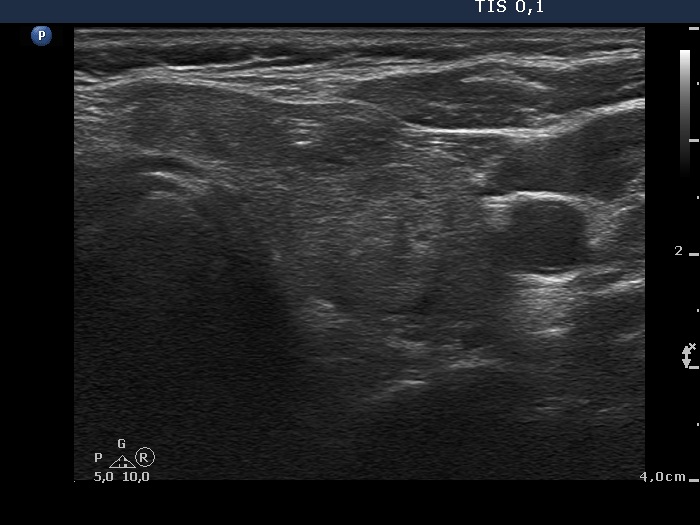

Right lobe, longitudinal scan

Left lobe, transverse view. There is an echonormal nodule in the central part of the lobe.